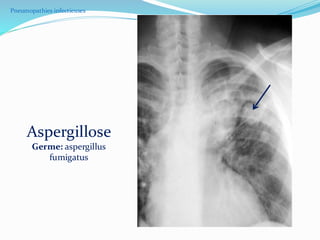

Aspergillose

Germe: aspergillus

fumigatus